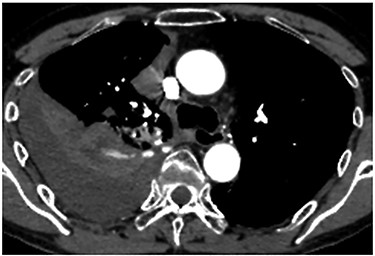

A 60-year-old man underwent right apical and posterior segmentectomies via VATS for early-stage lung cancer. The bronchus and pulmonary parenchyma were divided by endoscopic staples (Echelon®; Ethicon Endo-Surgery). The resected tumour was 1.5 cm in the longest diameter and pathologically diagnosed as Stage IA adenocarcinoma. The patient was discharged uneventfully on eighth day after surgery. Chest radiography revealed no significant findings, and laboratory data were within the normal ranges on the 14th day after discharge at a scheduled visit to the outpatient clinic. However, the patient was transported by ambulance to our hospital owing to a sudden onset of chest pain and dyspnoea on the 32nd day after discharge. He developed hypotension and tachycardia with systolic blood pressure of 50 mmHg and heart rate of 114 beats/min. The haemoglobin concentration level, which had been 12.3 mg/dl on the 14th day after discharge, decreased by 8.7 mg/dl. Chest radiography revealed a massive right pleural fluid, and enhanced computed tomography (CT) showed an extravasation of contrast media near the fifth thoracic vertebra (Fig. 1). The patient was diagnosed with haemothorax and an emergency operation was performed. Thoracoscopic examination revealed massive blood coagulation in the right thoracic cavity, with no adhesions. After removal of the coagulation, continuous active bleeding from the intercostal artery was found near the fifth thoracic vertebra in the vicinity of a stump of the bronchus divided by a staple (Supplementary Video 1). A thoracotomy through the fifth intercostal space was therefore performed to achieve haemostasis, and the bleeding was stopped by suturing using a 4–0 nonabsorbable monofilament ligature. In addition, the bleeding point was covered with a collagen-fibrin patch (Tachosil®). The posterior part of the staple line of the lung parenchyma adjacent to the bleeding point under full inflation was partly exposed, whereas the bronchial stump was covered with lung. Therefore, the scratching created by the staples was assumed to cause haemothorax. The total amount of haematoma in the right thoracic cavity and the intraoperative blood loss was 3980 g. Postoperative CT confirmed that the stapler dividing the lung parenchyma directly faced the bleeding point beside the fifth vertebra (Fig. 2). The patient progressed satisfactorily after the reoperation and was discharged on ninth day after reoperation.

Postoperative CT revealing that the stapler dividing the lung parenchyma directly touched the fifth vertebra (arrow).